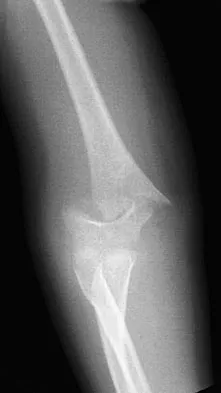

Wrist drop, characterized by the inability to extend the wrist and fingers, is a classic sign of radial nerve palsy. While other nerves can be injured in severe shoulder trauma or brachial plexus injuries, radial nerve compression or stretch is the most direct cause of wrist drop. This is a less common injury with isolated shoulder dislocation but can occur with associated humeral shaft fractures or severe traction.